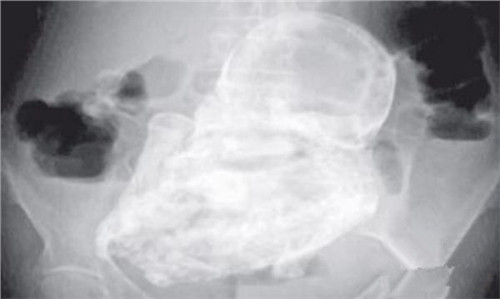

2、b超检查发现胎动、胎心消失,有的胎头已变形。